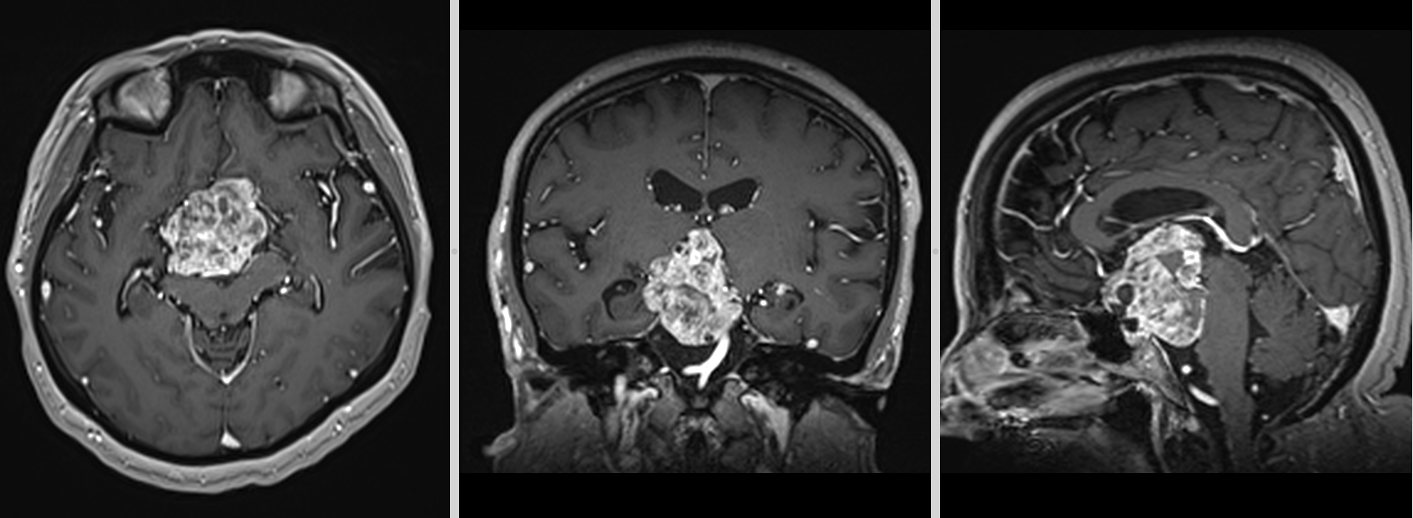

Localizare și creștere tumorală

Craniofaringioamele au localizare predominant supraselară, dar pot avea extensii variabile în zona selară, hipotalamică, chiasmatică și ventriculară. Frecvent, tumora comprimă structurile din vecinătate, inclusiv hipotalamusul, hipofiza, chiasma optică, arterele cerebrale anterioare și ventriculii laterali. Această poziționare explică simptomatologia complexă, care poate include tulburări endocrine, neurologice și vizuale.

- Imagistica cerebrală (RMN și CT) este esențială. RMN-ul evidențiază tumora în detaliu, oferind informații despre extindere și relațiile cu structurile adiacente. CT-ul evidențiază mai bine calcificările caracteristice craniofaringioamelor adamantinomatose.